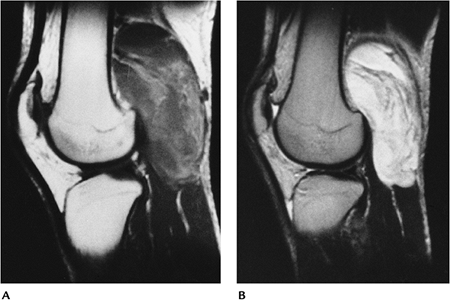

FIGURE 10-44 Intermediate-grade myxoid liposarcoma in the popliteal fossa. Sagittal T1-weighted (A) and T2-weighted (B) images showing little fat signal on T1-weighted (A) and increased signal intensity on the T2-weighted image (B).